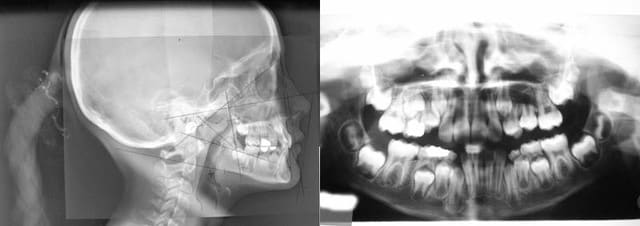

par exemple

Rx - Eugenol

Depart 1 y9ttvq - Eugenol

Materiel  1 efp0tb - Eugenol